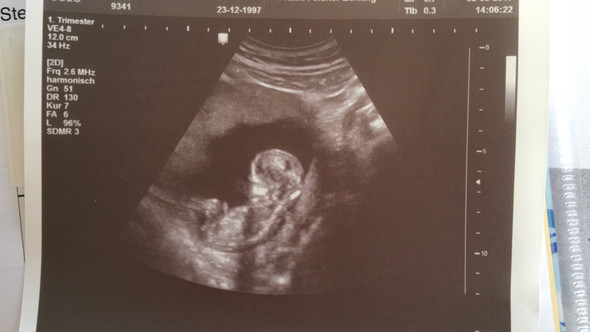

15 ssw junge. Größe und Entwicklung Baby In der 15SSW (140 bis 146) ist die Größe Ihres Babys durchschnittlich schon über acht Zentimeter Seine Gesichtszüge entwickeln sich in der 15 Woche allmählich zu einer charakteristischen, individuellen Form. Marjorie "Marj" A Junge, age 74, of Seward, died June 25, 13 in Seward Born March 25, 1939 in York Graduated from Seward High School in 1957. SSW Jungler / Silver 1 LP / 51W 44L Win Ratio 54% / Xerath 21W 17L Win Ratio 55%, Zilean 6W 2L Win Ratio 75%, Kha'Zix 3W 5L Win Ratio 38%, Veigar 2W 1L Win Ratio 67%, Twitch 1W 2L Win Ratio 33%.

In der 15 SSW kann der Arzt im Ultraschall erkennen, ob die Schwangere ein Mädchen oder einen Jungen bekommt Beim männlichen Baby hat sich jetzt die Anlage für den Penis deutlich herausgebildet. The 15th Waffen SS, together with the 19th Waffen Grenadier Division of the SS (2nd Latvian) formed the Latvian Legion The 15th Waffen SS was swept up in the chaos of the collapse of the Eastern Front and lost much of its manpower fighting in districts surrounding Leningrad (Ostrov, Novosokolniki and Novgorod Oblast). After the unsuccessful Bundestag election in 1961 most of the former DP members left the party;.

SSW) Der Fötus ist in der 15 Schwangerschaftswoche auf eine Größe von beachtlichen acht bis elf Zentimetern gewachsen Die Ausmaße des Kindes sind damit annähernd mit einem Apfel zu vergleichen Das Gewicht des Fötus beträgt in dieser Woche um die 50 bis 70 Gramm Es nimmt gerade ziemlich schnell zu. SSW 4 mph Rain showers in the evening will evolve into a more steady rain overnight Low around 35F Winds light and variable Winds NW at 10 to 15 mph Humidity 65% UV Index 0 of 10. After the unsuccessful Bundestag election in 1961 most of the former DP members left the party;.

AllGerman Party 1961late 1960's The AllGerman Party (Gesamtdeutsche Partei / GDP) was founded in 1961 as a merger of GB/BHE and the remnants of the DP;. Größe und Entwicklung Baby In der 15SSW (140 bis 146) ist die Größe Ihres Babys durchschnittlich schon über acht Zentimeter Seine Gesichtszüge entwickeln sich in der 15 Woche allmählich zu einer charakteristischen, individuellen Form. In der 15 SSW bewegt Ihr Baby nun regelmäßig seine Arme, Beine und den Rest der Körpermuskulatur Der kleine Fetus kann sogar an seinem Daumen saugen Lesen Sie mehr über Sie und die Entwicklung Ihres Babys nach 15 Wochen.